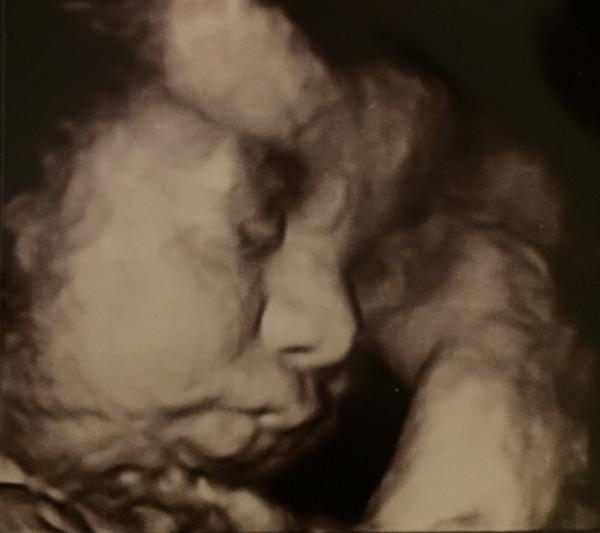

Hallo ihr Lieben, wir waren heute wieder beim Arzt. CTG war alles gut, ein paar Wehen waren drauf und der KrĂŒmel hat fleißig getobt Laut Messung ist der KrĂŒmel heute bei 34+3 bereits 48cm groß und 1900g schwer...eine Mopsbacke also Er ist somit etwa 1 1/2 Wochen weiter Auf meiner Überweisung zur Geburtsplanung steht nun Verdacht auf fetale Makrosomie mit der Bitte um Kontrolle der Maße vom KrĂŒmel. Den Termin hab ich am 12.12. Wir sind nun sehr gespannt, eventuell muss eingeleitet werden, wenn der KrĂŒmel so weiter wĂ€chst Das es nun stagniert ist ja wohl eher nicht drin, oder? Auf Einleitung hab ich ja so gar keine Lust drauf Ich wollte doch eine selbstbestimmte Geburt mit möglichst wenigen Eingriffen von außen Ich hab nun meinem Mann schon damit gedroht, dass wir ab 37+0 dann tĂ€glich herzeln Der HimbeerblĂ€ttertee steht auch schon im Schrank und die Akkupunkturtermine sind gemacht. Anbei noch das heutige Foto von der kleinen Mopsbacke Mama & Papa sind schon total verliebt in dich, Babyboy

Bild zu ZurĂŒck vom Arzt...Mopsbacken-Alarm 🙈 - Forum fĂŒr Januar - Mamis

Mach dir keine Sorgen, nach Mutterschaftsrichtlinie wird GrĂ¶ĂŸe und Gewicht nach dem 3. Screening erst ab ET wieder gemessen. Die Messung ist so ungenau, das beunruhigt nur. Solange es deinem Zwerg gut geht, ist doch alles top Wunderschönes Bild ĂŒbrigens!